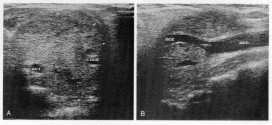

LINFOMA MALIGNO DEL BAZO

El linfoma maligno del bazo. Tumor maligno en general y especialmente el formado por células epiteliales, a saber. Los canceres se dividen en dos grandes categorías de carcinoma y sarcoma u otros. La característica básica de la malignidad es una anormalidad de las células, transmitida a las células hijas, que se manifiesta por la reducción  del control del crecimiento y …